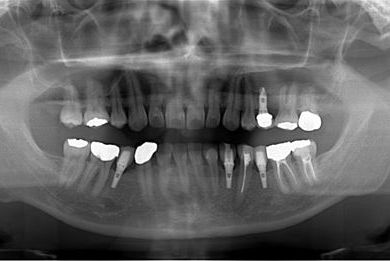

インプラントの症例写真 IMPLANT

骨再生インプラント治療

| 性別/年齢 | 男性 / 34歳 | ||||||||||||||||||||||||||||||||

| 治療方針 | ソケットリフトにて上顎洞を拳上し、インプラント治療を可能にする。 | ||||||||||||||||||||||||||||||||

| 治療内容 | インプラント1本(ソケットリフト)、メタルボンドセラミッククラウン1本 | ||||||||||||||||||||||||||||||||